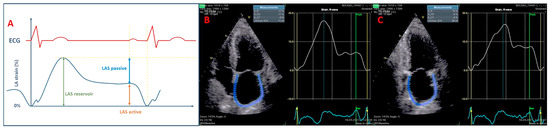

- Gan, G.C.H.; Ferkh, A.; Boyd, A.; Thomas, L. Left atrial function: Evaluation by strain analysis. Cardiovasc. Diagn. Ther. 2018, 8, 29–46. [Google Scholar] [CrossRef]